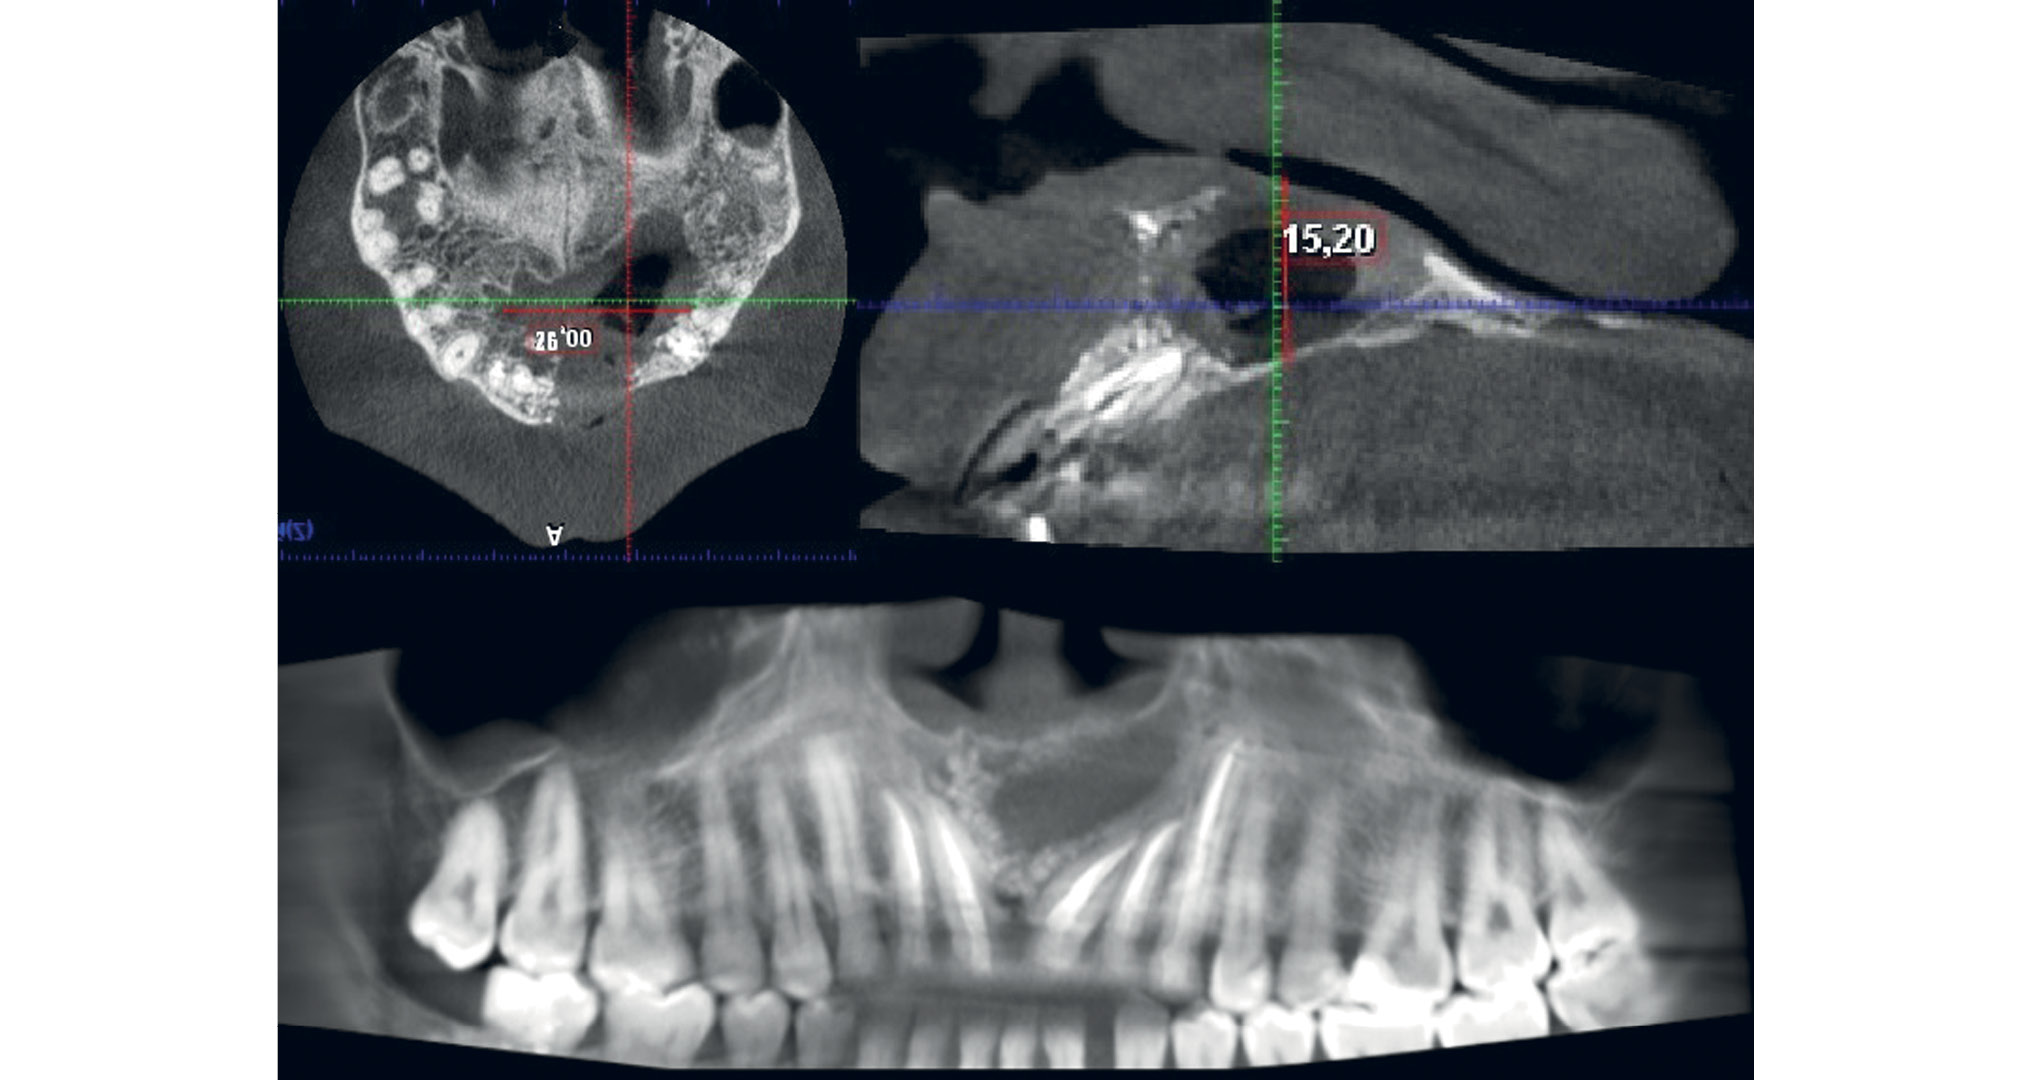

По данным конусно-лучевой компьютерной томографии: в результате операции сформировался чуть более расширенный левый носовой ход за счет перевода костной полости в полость левого носового хода. Содержимое костной полости однородное. Наблюдается значительное уменьшение размеров костной полости (рис. 6–8).

Рис. 6. Пациент Д., 33 года: данные конусно-лучевой компьютерной томографии. Состояние костной полости через 3 мес после последнего оперативного лечения

Рис. 7. Пациент Д., 33 года: данные конусно-лучевой компьютерной томографии. Состояние полости дефекта через 9 мес после последнего оперативного вмешательства